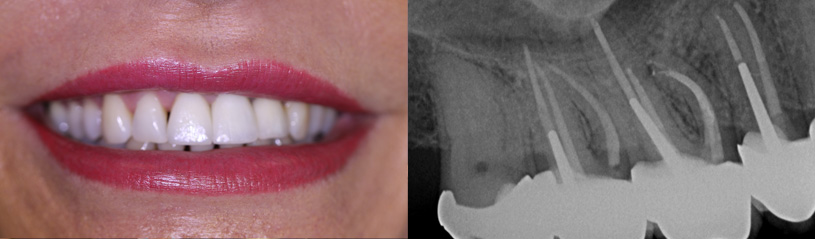

Bereits nach der ersten Behandlung stellte sich eine deutliche Verbesserung ein. Heute, ein halbes Jahr später, habe ich die Röntgenbilder gesehen und ich empfinde es als medizinisches Wunder. Dr. Eggert hat meine Backenzähne gerettet und ich bin absolut schmerzfrei.

Mein Zahn konnte dank der guten Arbeit von Dr. Eggert gerettet werden, die Entzündung im Knochen ist vollständig abgeheilt. Die Unterschiede vorher - nachher werden anhand der digitalen Röntgenaufnahmen auch für den Laien deutlich.